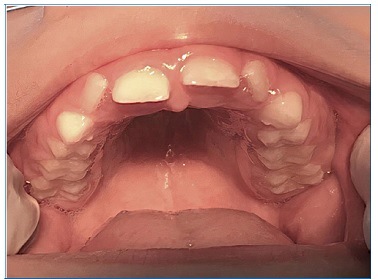

Intraoral examination revealed the presence of gingival hyperplasia in the upper arch and gingivitis associated with the presence of dental biofilm, arched palate, Angle class I occlusion without crossbite or open bite, dolichofacial pattern, labial hypotonia, and mild enamel hypomineralization (presence of whitish-cream demarcated opacities)14 in the permanent maxillary central incisors (Figures 4 and 5). Moreover, she had caries lesions in the deciduous mandibular left second molar and mandibular first permanent molar, which presented great coronary destruction and pulp involvement (Figures 6 and 7).

Figure 4 Gingival hyperplasia in the upper arch and gingivitis associated with the presence of dental biofilm, arched palate